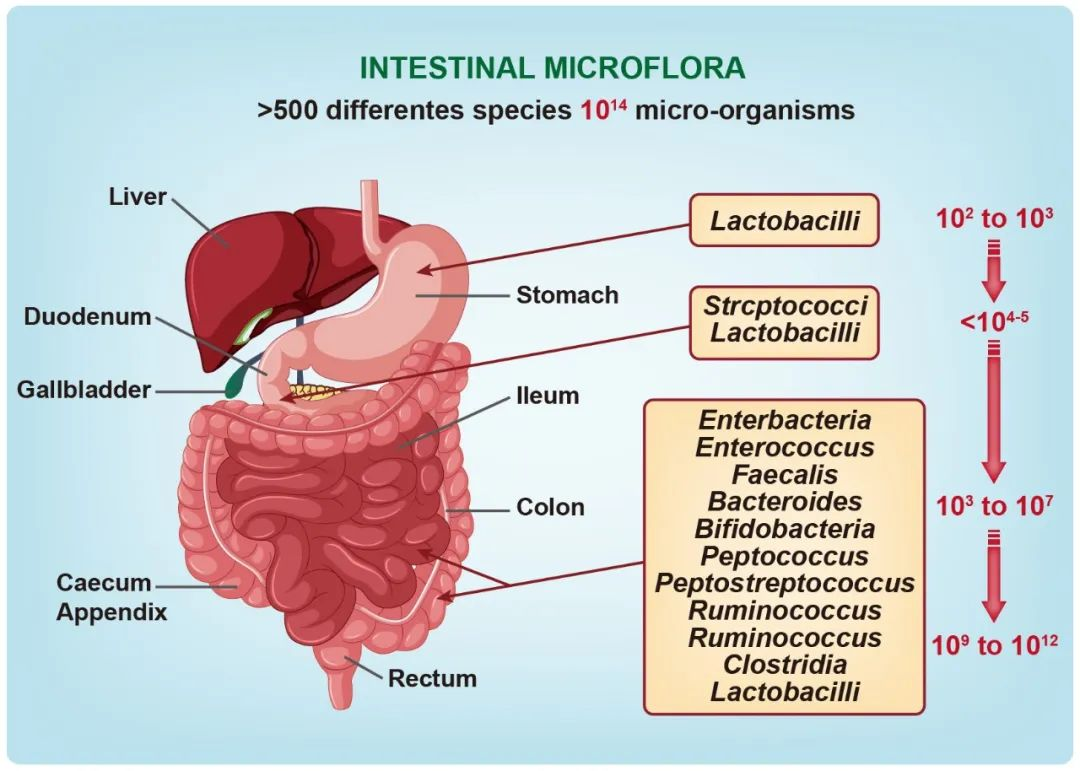

论文插图设计

滑动查看更多 点击查看大图